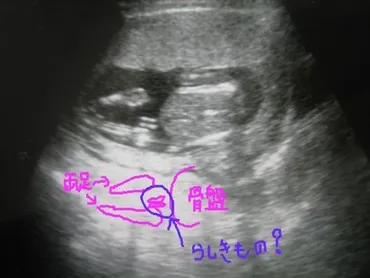

✅ 病院でエコー検査を受け、赤ちゃんの心臓の動きや足の動きを確認し、その様子に感動した。

✅ 15週のため性別はっきりとは断定できなかったものの、男の子の兆候が見られる可能性があり、夫は喜んでいた。